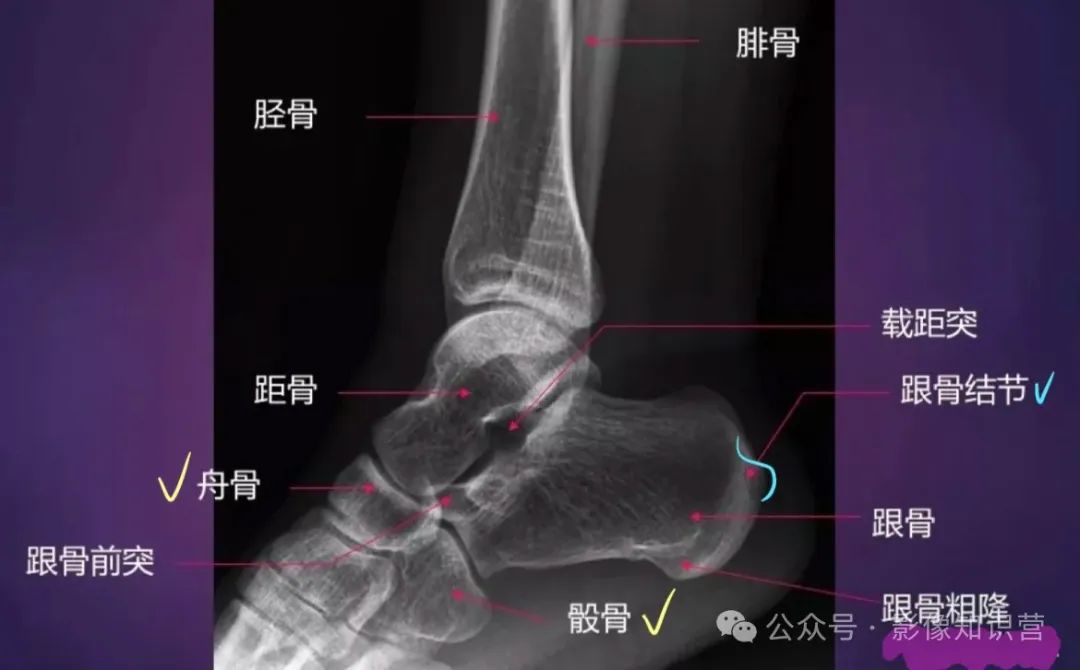

踝关节

骨骼组成:胫骨远端(内踝)、腓骨远端(外踝)、距骨。

影像特征:X线正侧位:观察踝穴(距骨与内外踝的匹配)及下胫腓联合宽度(正常<6mm)

足部

骨骼组成:跗骨(7块:距骨、跟骨、足舟骨、骰骨、3块楔骨)。跖骨(5块)、趾骨(14块)。

跟骨骨折需评估Böhler角(正常20°-40°),角度减小提示压缩性骨折。